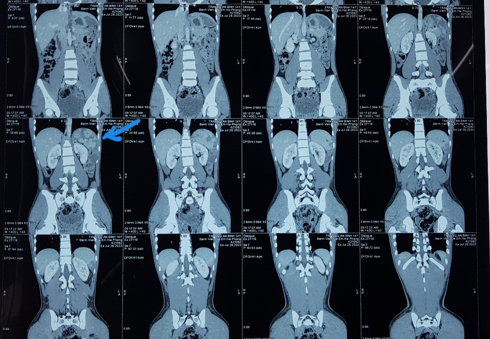

được cơm, không nôn, không sốt. Kết quả CT ổ bụng lần 2 cho thấy tổn thương

lách đã phục hồi tốt, khối máu tụ giảm kích thước và các mảnh lách vỡ đang liền

lại (Hình 2).

Hình 2: Phim chụp CT ổ bụng

sau điều trị 14 ngày, mũi tên chỉ vị trí vỡ lách, các mảnh vỡ đang liền, khối

máu tụ co nhỏ lại.